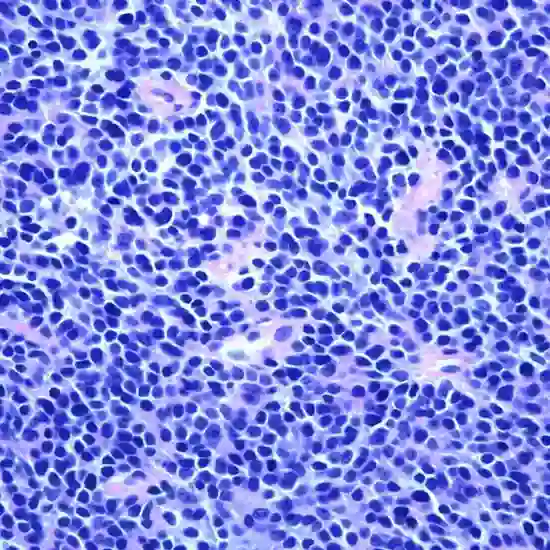

Ewing Sarcoma

Ewing sarcoma is a rare type of malignant bone cancer that primarily affects children and young adults. It is aggressive cancer that typically arises in the bones, but can also occur in soft tissues. Ewing sarcoma most commonly occurs in the long bones of the body, such as the femur (thigh bone), tibia (shin bone), and humerus (upper arm bone), but it can also occur in other bones or soft tissues, such as the pelvis, ribs, spine, or muscles.

Diagnosis of Ewing sarcoma usually involves a combination of imaging studies such as X-rays, CT scans, MRI scans, and bone scans, as well as a biopsy to confirm the presence of cancerous cells. Treatment for Ewing sarcoma typically involves a combination of chemotherapy, radiation therapy, and surgery, depending on the size, location, and stage of the tumor.